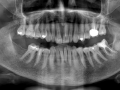

Rozległa torbiel zawiązkowa żuchwy

Paulina Adamska, Maria Mikołajska, Anna Janowska, Anna Starzyńska